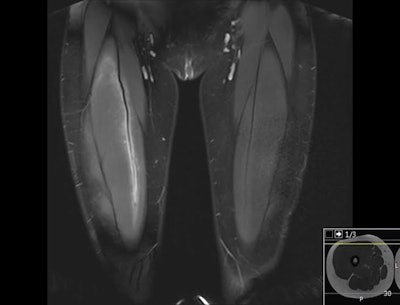

I have worked a lot with hip, knee, and ankle imaging, especially MRI. Injury to the cruciate ligaments, posteromedial and posterolateral corner of the knee has been a special interest, as well as injuries around the ankle. However, the spectrum of sports injuries covers all joints, both upper and lower limb, and every day there is a new challenge and something new to learn.

Imaging can detect both subtle and obvious injuries associated with sporting activity. Early stress reactions in bone, tendons, and soft tissues can be seen, as well as all sorts of ruptures and fractures. However, some injuries are subtle, and if you don't look for them, you will not find them. A sports radiologist must look for smaller changes than other radiologists are used to. This may be because the athlete is imaged very early after an injury or after the start of a complaint, and smaller injuries may be more important in an athlete than in other patients.